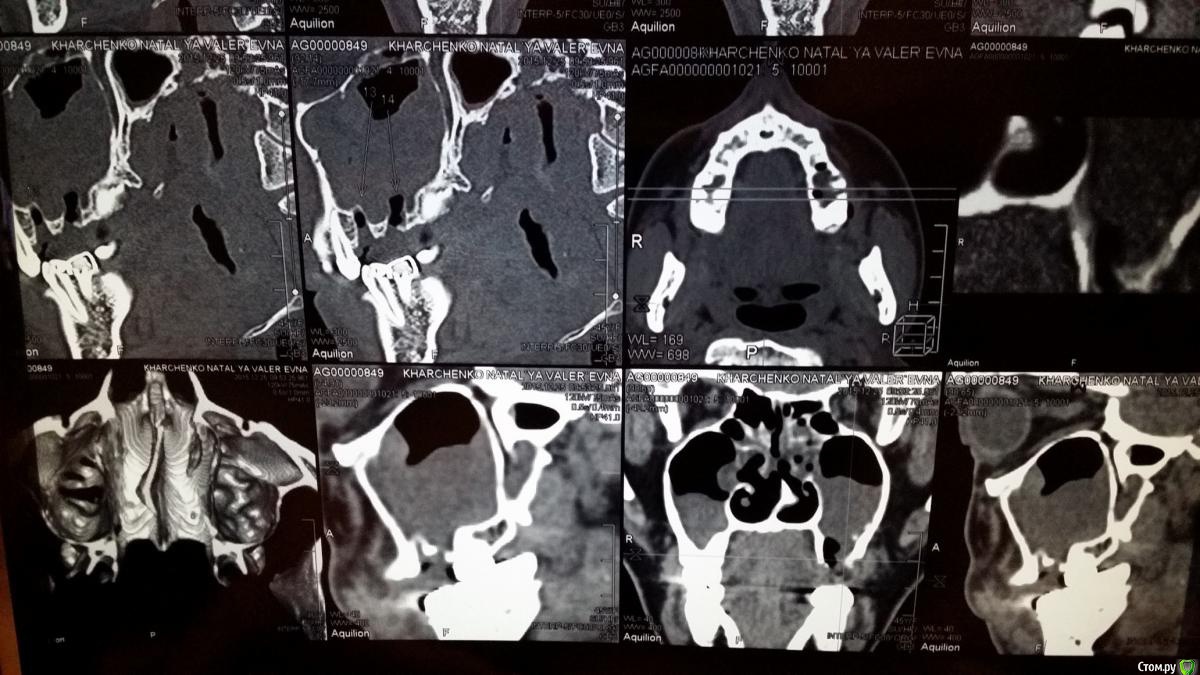

natali777 Опубликовано 6 января, 2016 Автор Поделиться Опубликовано 6 января, 2016 кт на 5 день после удаления Ссылка на комментарий

natali777 Опубликовано 6 января, 2016 Автор Поделиться Опубликовано 6 января, 2016 кт ппн после удаления 5 и 6 зубов Ссылка на комментарий